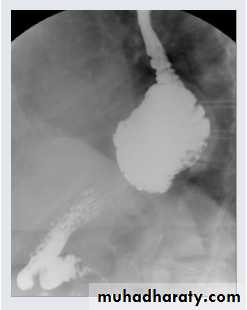

PA chest X-ray: A smooth-contoured cavity of 5 cm diameter, containing gas fluid level, is visible behind the heart shadow (arrow). This lesion is the gas-containing fornix protruding into the chest cavity through the esophageal hiatus.

A barium swallow study demonstrates a large hiatal hernia with the majority of the stomach in the chest, not in the abdomen where it belongs.